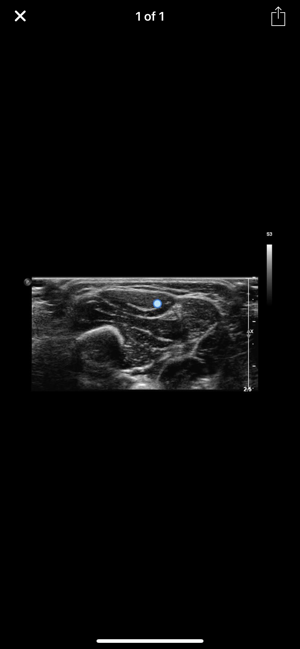

• Improve your skills in identifying muscles and neighbouring structures using ultrasound! • Instructive ultrasound cross-sectional images and videos• Plus: cross sections, scouts and the option for individual annotations• Use it as a Point-of-care APP on your smart phone or as a reference APP for anatomical studies. • Online content for quick reference and updates. Download option for permanent availabilityEntwickler App: Quickbird Studios GmbH, www.quickbirdstudios.comEntwickler Content: Child & Brain GmbH, www.childandbrain.com